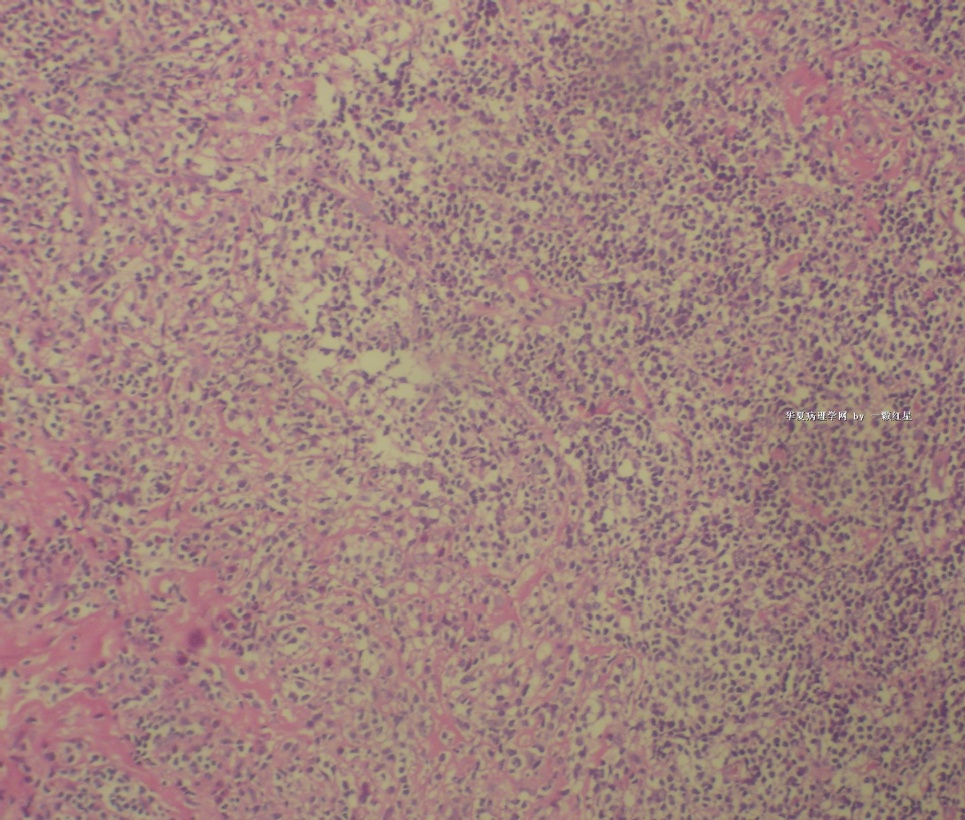

标本名称:  左前臂数个大小不等的皮下肿物。

既往有非何杰金淋巴瘤(滤泡性淋巴瘤)病史22个月。

• 左前臂数个大小不等的皮下肿物     淋巴瘤?图2

图2

病例不错。细胞胞浆透亮,间质血管丰富,图片不是很清晰,似乎有嗜酸粒细胞?

恶性,首先考虑T-NHL。IHC证实。

既往有NHL病史,图片不太清晰,细胞弥漫,胞浆透亮,首先考虑T细胞淋巴瘤。